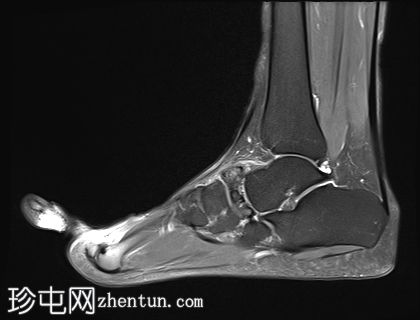

矢状面

T2

舟骨呈二分状,分为两个骨块——较大的内侧骨块和较小的外侧骨块。

内侧骨折块外侧面呈“逗号状”,舟骨相对于距骨头轻微向内移位。

外侧骨折块及其外侧均呈斑片状T1低信号和PD FS高信号,并伴有硬化和微小囊肿,提示软骨联合/纤维界面存在慢性应激反应或退行性改变,可能伴有缺血性坏死。

双分舟骨区域外未见急性骨折线或骨髓水肿。

周围跗骨和关节未见明显异常。

未见明显软组织异常或关节积液。